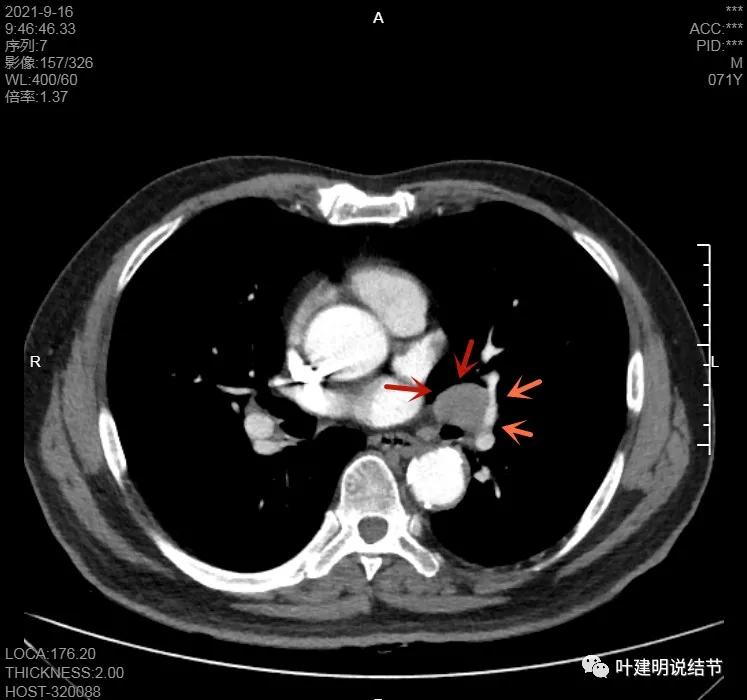

上图示病灶在左下叶,红色所指的与绿色箭头所指的是两个病灶,不相连的,实性结节

上图也示病灶是两个的,小的与大的之间有间隙的。大的病灶呈长方形似的

左下病灶在增强CT中强化不明显,但有肺门区肿大淋巴结,而且近3厘米大。同事叫我看片子的时候,本来只先看左下病灶处,以为是良性结节。但翻到肺门区,发现有如此大的肿大淋巴结,那这个原发灶则肯定是恶性的了!我们先来看纵隔窗的淋巴结情况: